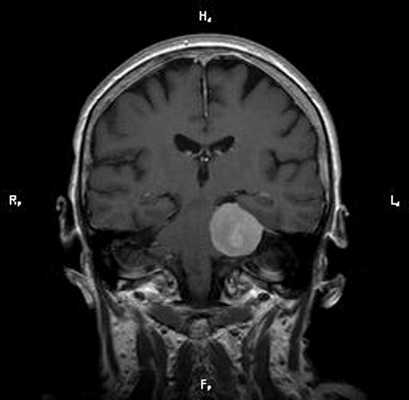

Пациент Р. 62 лет

Проблема: жалобы на частые головные боли, снижение слуха (левое ухо), а также шум в ушах (больше слева). Пациент был направлен на МРТ головного мозга в ЦМРТ с целью уточнения диагноза.

Диагноз: Онкология. Менингиома мосто-мозжечкового угла

При МРТ головного мозга в левом мосто-мозжечковом углу определялось больших размеров округлой формы внемозговое патологическое образование, с четкими ровными контурами, широким основанием, прилежащее к твердой мозговой оболочке. После внутривенного контрастирования отмечалось равномерное, выраженное усиление интенсивности МР-сигнала от вышеописанного образования, а также твердой мозговой оболочки. Пациенту был поставлен диагноз (менингиома левого мосто-мозжечкового угла).